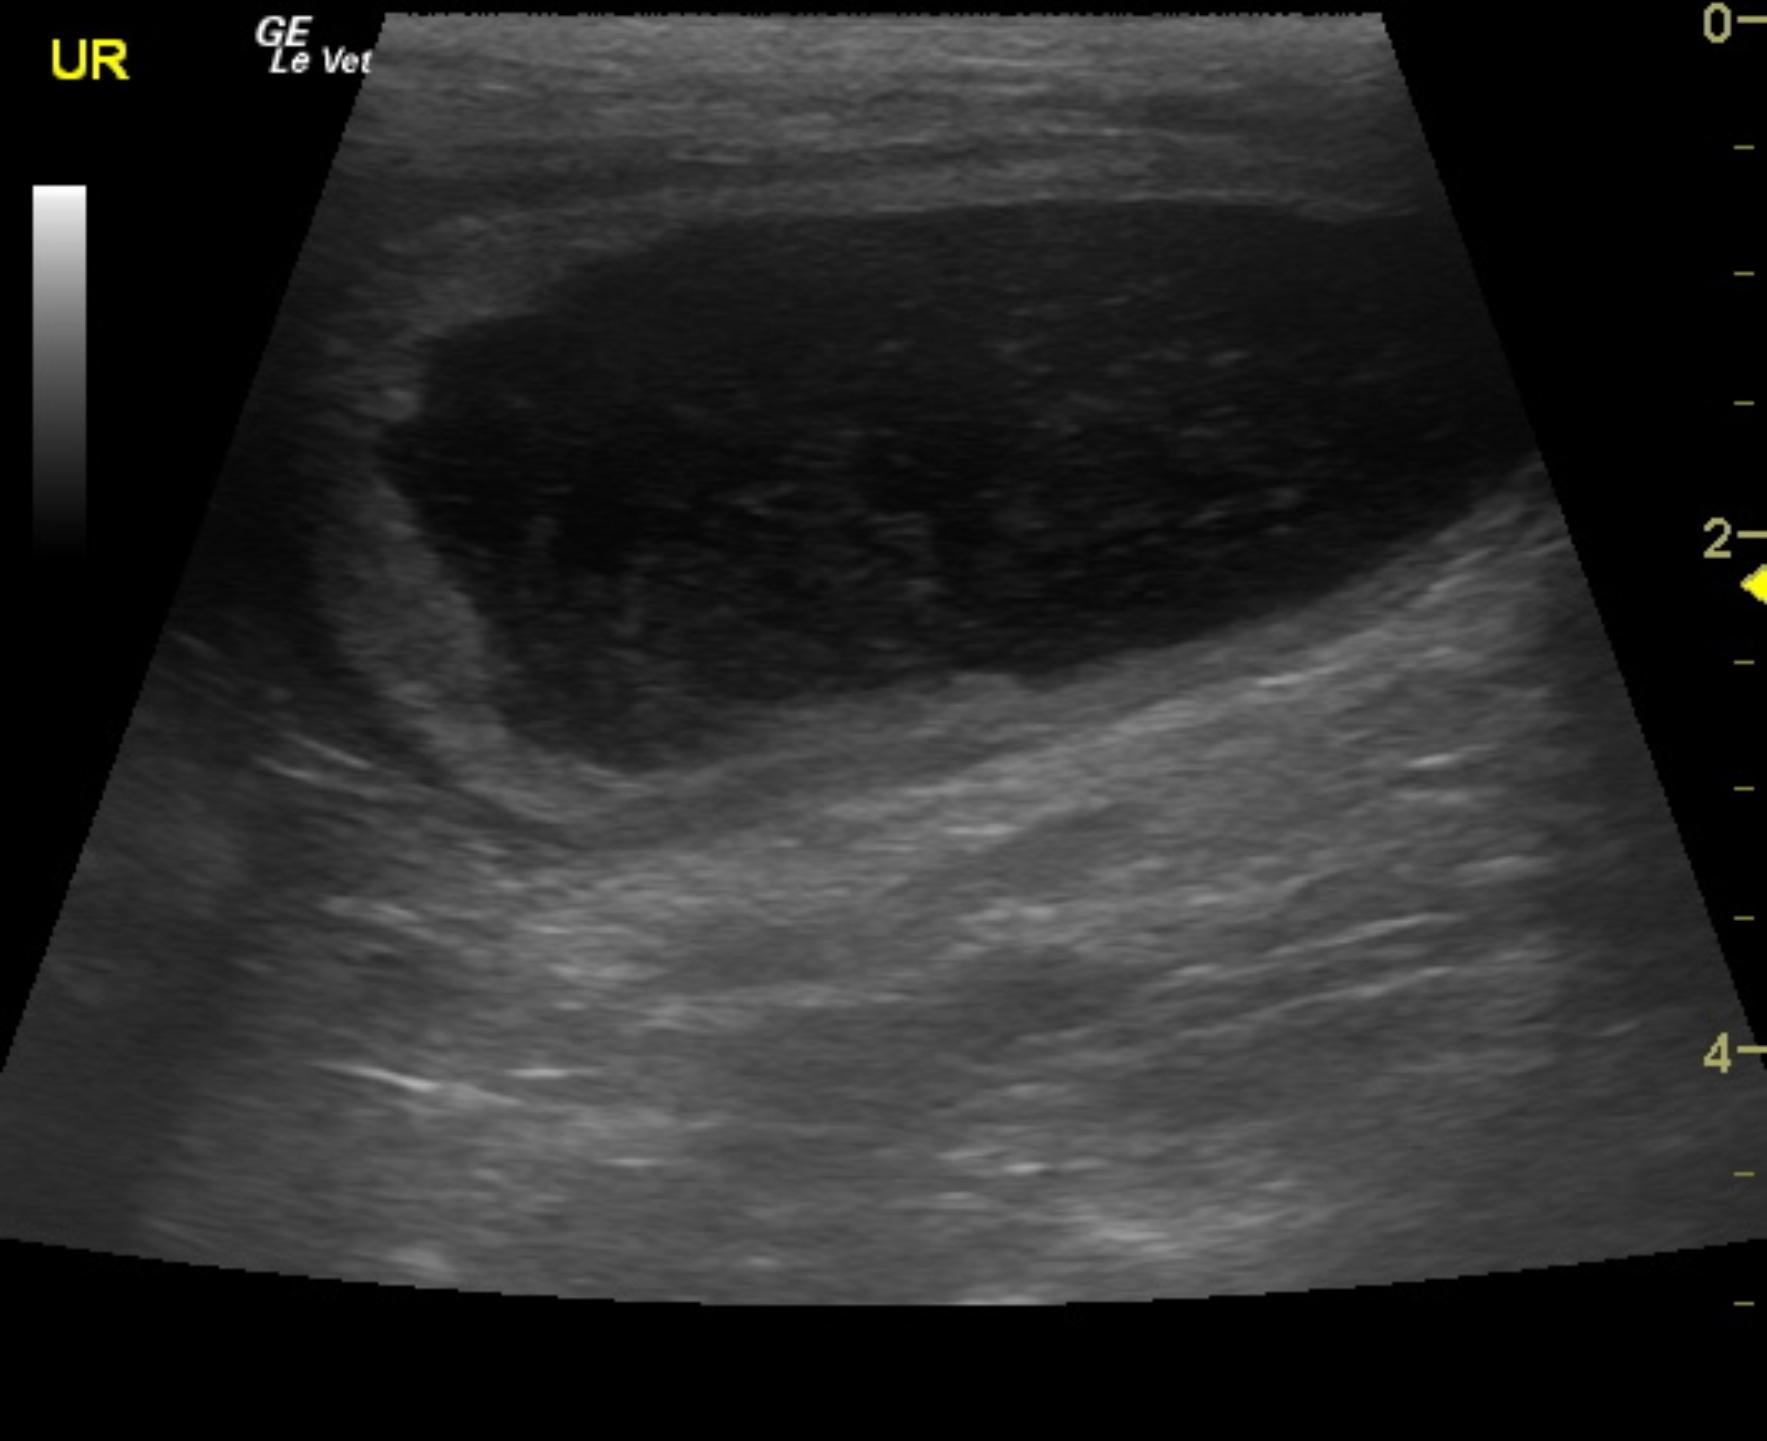

A 9-year-old spayed female Welsh Corgi dog was presented for evaluation for recurrent hematuria. On urinalysis, inappropriate SG (1.020) and proteinuria were present. Urine culture revealed Acinetobacter, Pseudomonas, and Enterobacter; the latter two were antibiotic resistant strains.